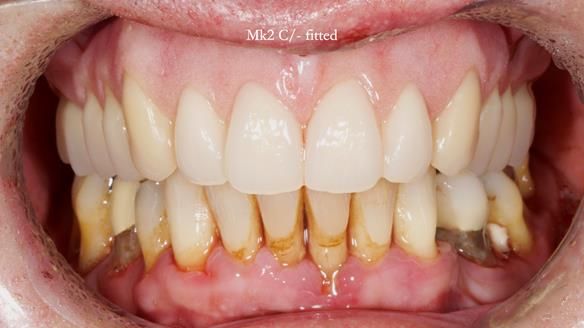

Jeremy’s upper bridge, supported by the canine teeth (13 and 23), was failing both aesthetically and functionally.

- On smiling, the bridge was clearly visible and did not look natural, as the ceramic had been ground back.

- Functionally, the bridge was unstable, due to Periodontitis – Stage IV, Grade C (generalised).

- The upper molars (UR7 and UL7) had also failed and required removal.

- Periodontal therapy was carried out to help maintain the lower teeth for as long as possible.